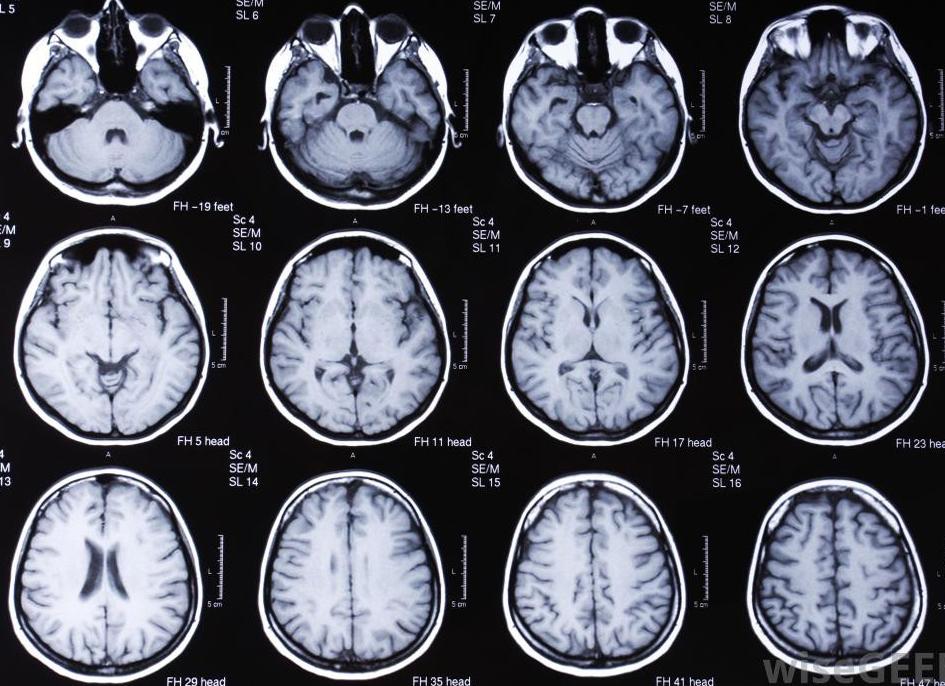

Наиболее распространенными на сегодняшний день методами с высокой точностью диагностики являются МРТ (магнитно-резонансная томография) и КТ (компьютерная томография).